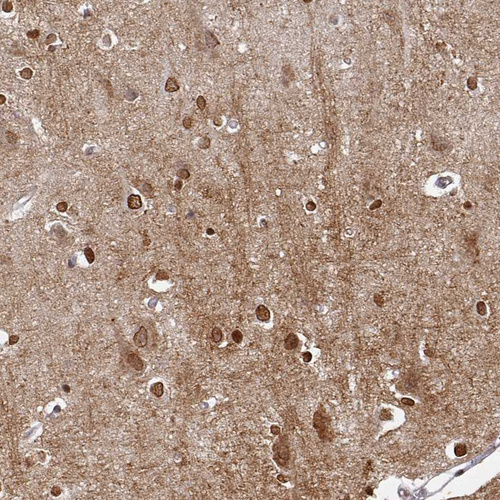

Immunohistochemistry analysis in human cerebral cortex and liver tissues using HPA008206 antibody. Corresponding OMG RNA-seq data are presented for the same tissues.